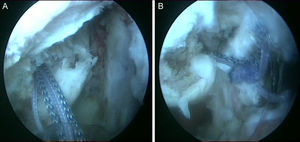

Técnica quirúrgicaBajo anestesia general y locorregional (bloqueo interescalénico), se intenta reducir el hombro de forma cerrada. En caso de no conseguirlo se coloca al paciente en decúbito lateral con tracción de unos 5kg y, siguiendo la técnica descrita por Verma5, se introduce un «Wissinger» por el portal posterior estándar, el que empleamos para la artroscopia de hombro. Con el «Wissinger» a través del portal realizamos tracción de la cabeza humeral hacia lateral, apoyándonos en la cápsula y en la parte posterior del manguito, no en el hueso. Habitualmente con esta maniobra conseguimos introducir la cabeza humeral en la glenoides y podemos pasar a realizar la artroscopia de hombro. En caso de no conseguir una reducción, pasaríamos a realizar una reducción abierta con el paciente en posición de silla de playa y con una vía de abordaje anterior al hombro. Con el hombro reducido se realiza la artroscopia de hombro. Se emplean los portales posterior, anterosuperolateral, anterior, portal de Wilmington y portal posteroinferior. Se estudia la lesión de Hill-Sachs inverso, la relación con el tendón del subescapular y la lesión del labrum posterior (fig. 2, figs. 3 y 4), el resto del labrum y el manguito de los rotadores. Hay que limpiar bien la articulación, extirpar todo el tejido fibroso, liberar el labrum posterior de las adherencias a la glena, preparar el lecho óseo de la glena antes de colocar los implantes (en el caso 1 se emplearon 2 implantes Lupine BR [DePuy Mitek, Raynham, MA], y el caso 2 con un Gryphon BR [DePuy Mitek, Raynham, MA] cargado con doble sutura), realizar la reconstrucción capsulolabral con un pasador directo o indirecto, anudar y cortar las suturas. Una vez reparadas las lesiones soltamos el brazo del sistema de tracción y comprobamos la relación de la cabeza humeral, del defecto óseo anterior con la glenoides, al hacer rotaciones del hombro (sobre todo si hay riesgo de «enganche» con la rotación interna), y decidimos si fijamos el tendón del subescapular en el defecto óseo humeral anterior, tal y como describió Krackhardt6.

No es estrictamente necesario que reproduzcamos un enganche de la lesión de Hill-Sachs inversa para decidir realizar el remplissage inverso. Con la óptica en el portal anterosuperolateral liberamos el tendón del subescapular, su cara anterior y posterior. Preparamos el lecho óseo de la cabeza humeral, extirpando todo el tejido fibroso de la lesión de Hill-Sachs inversa, con el sinoviotomo, la fresa de hueso o periostotomos, hasta obtener hueso sangrante. Entonces desde el portal anterior, insertamos los implante en el defecto óseo (en el caso 1 un 5,5 Healix BR [DePuy Mitek, Raynham, MA] con 2 suturas UHMWPE [Orthocord; DePuy Mitek]) en el tercio superior y en la zona más medial del defecto (fig. 5), y en el caso 2 insertamos 2 Gryphon BR Healix BR (DePuy Mitek, Raynham, MA) con 2 suturas UHMWPE (Orthocord; DePuy Mitek), uno inferior y otro superior en la zona más medial del defecto óseo. Recuperaremos las suturas desde un portal anterosuperior accesorio y con una pinza para atravesar el tendón (Penetratror DePuy Mitek, Raynham, MA) a través del portal anterior, atravesamos el tendón del subescapular y recuperamos las suturas. Daremos puntos colchoneros, uno inferior y otro superior, para conseguir un buen contacto del tendón con el hueso, separando los puntos entre 1 y 2cm (fig. 6). Podemos ayudarnos con un empujanudos a través del portal anterosuperior accesorio para el manejo y recuperación de las suturas, acercándolas a la boca de la pinza penetrator, tratando de no mover en exceso la pinza una vez atravesado el tendón, para evitar lesionar el tendón y el cartílago. Manteniendo el brazo en 35-40° de rotación interna anudamos primero el punto inferior y luego el superior (figs. 7 y 8).

Caso 1, hombro derecho. A. Vista desde el portal ASL de la lesión de Hill-Sachs inversa con el implante en el tercio medial del defecto óseo. B. Imagen después de hacer los nudos; podemos ver el tendón del subescapular rellenando parcialmente el defecto óseo de la cabeza humeral, con la cabeza centrada en la cavidad.

Caso 2, hombro izquierdo. A. Visión desde el portal ASL de la cara posterior del subescapular con los 2 implantes en la parte inferior y superior del defecto óseo. B. Imagen tras el anudado del punto más inferior. C.

Imagen de la cara anterior del subescapular tras el anudado del segundo punto.